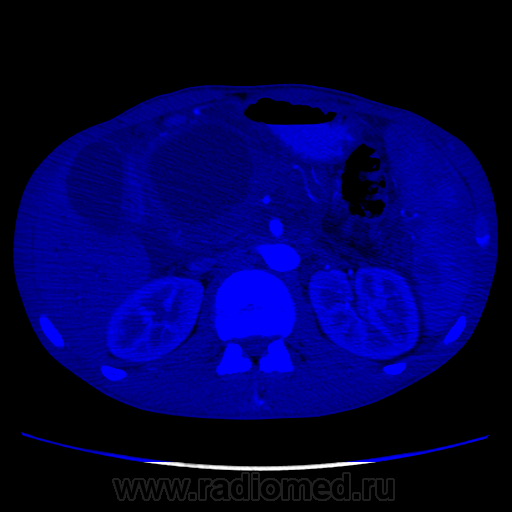

Видео крутит быстро. В головке плджелудочнгой железы кистозное образование с неравномерной толщины капсулой, наличием перегородок и солидного компонента. Печёночные желчные протоки, холедох значительно расширины. Вирсунгов проток расширен. Начальные отделы воротной вены сужены, возможно есть прорастание, не могу уследить. Итого: макрокистозная цистаденома (возможно уже цистаденокарцинома)

Не вижу, честно говоря, ни перегородок, ни солидного компонента. Вижу несколько (кажется, 3, но крутит очень быстро) кистозных образования в головке поджелудочной с относительно равномерно утолщенной капсулой. Плюс - неравномерное расширение Вирсунгова протока, инфильтрация перипанкреатической клетчатки и выпо в брюшной полости. Все укладывается в картину хронического панкреатита в стадии обострения с образованием псевдокист в головке железы.

Молодой человек никогда не болел панкреатитами, спросил были ли периоды сильных болей в животе вообще - говорит "не припомню", не выпивающий и тп. Сейчас клиника - боли, плохие анализы биохимии крови (не помню уже какие). Для псевдокист всё подходит, кроме клиники... Не очень представляю я себе, чтобы такой бессимптомный острый процесс, который тут якобы был, который сформироваться бы в такие псевдокисты... Причем самая крупная киста достаточно прилично деформирует прилежащие структуры, что тоже далеко не частое явление при псевдокистах. Далее... Капсула(псевдокапсула) довольна толстая, в артериальную фазу в ней мелькают маленькие артериальные сосуды. В настоящий момент изменения по типу "панкреатита" могут быть вторичными. В общем, не знаю. Почти убедили, что это псевдокисты. Как быть с анамнезом - сомнительно. Все врут.